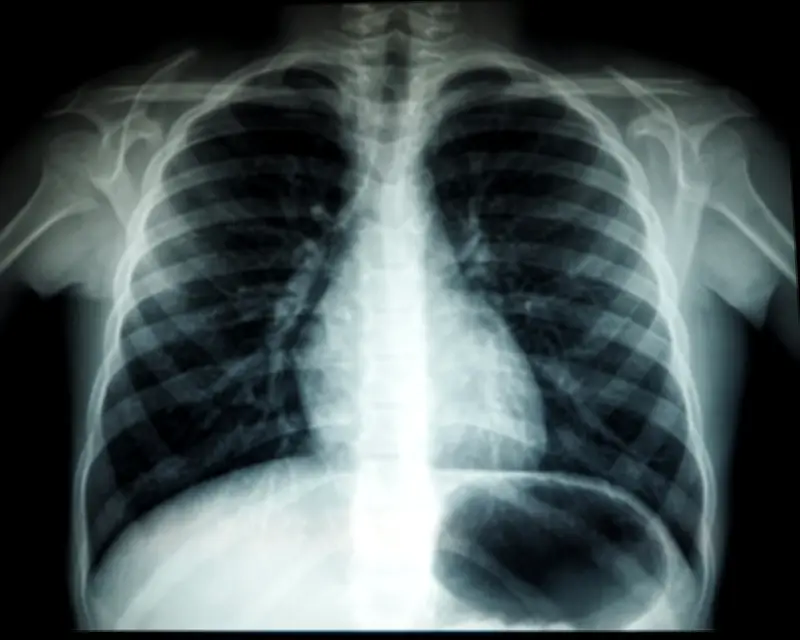

Pejabat Kesihatan Daerah Pontian telah mengesahkan bahawa seorang murid lelaki sekolah rendah dari daerah tersebut telah dijangkiti tuberkulosis selepas ujian menunjukkan keputusan positif untuk penyakit pernafasan itu.

Pejabat kesihatan daerah telah menjalankan saringan kesihatan terhadap murid-murid lain yang dikenal pasti sebagai kenalan rapat berikutan pengesanan kes tersebut di sebuah sekolah rendah di Pontian. Ini merupakan kes pertama individu di luar zon wabak tuberkulosis di Kota Tinggi yang telah dijangkiti penyakit berjangkit tersebut.

Kejadian ini berlaku selepas enam murid dari beberapa sekolah di Kota Tinggi dijangkiti tuberkulosis minggu lepas dan sedang menjalani rawatan. Pada Khamis lalu, enam murid di Kota Tinggi disahkan positif TB selepas saringan kenalan rapat yang dijalankan oleh Kementerian Kesihatan berikutan wabak di salah satu lokaliti daerah tersebut.

Setakat semalam, situasi tuberkulosis di Kota Tinggi dilaporkan berada di bawah kawalan dengan mereka yang terjejas menerima rawatan dan pemantauan rapi. Pengesanan kes di Pontian ini menandakan perkembangan baru dalam penularan penyakit tersebut di negeri Johor.